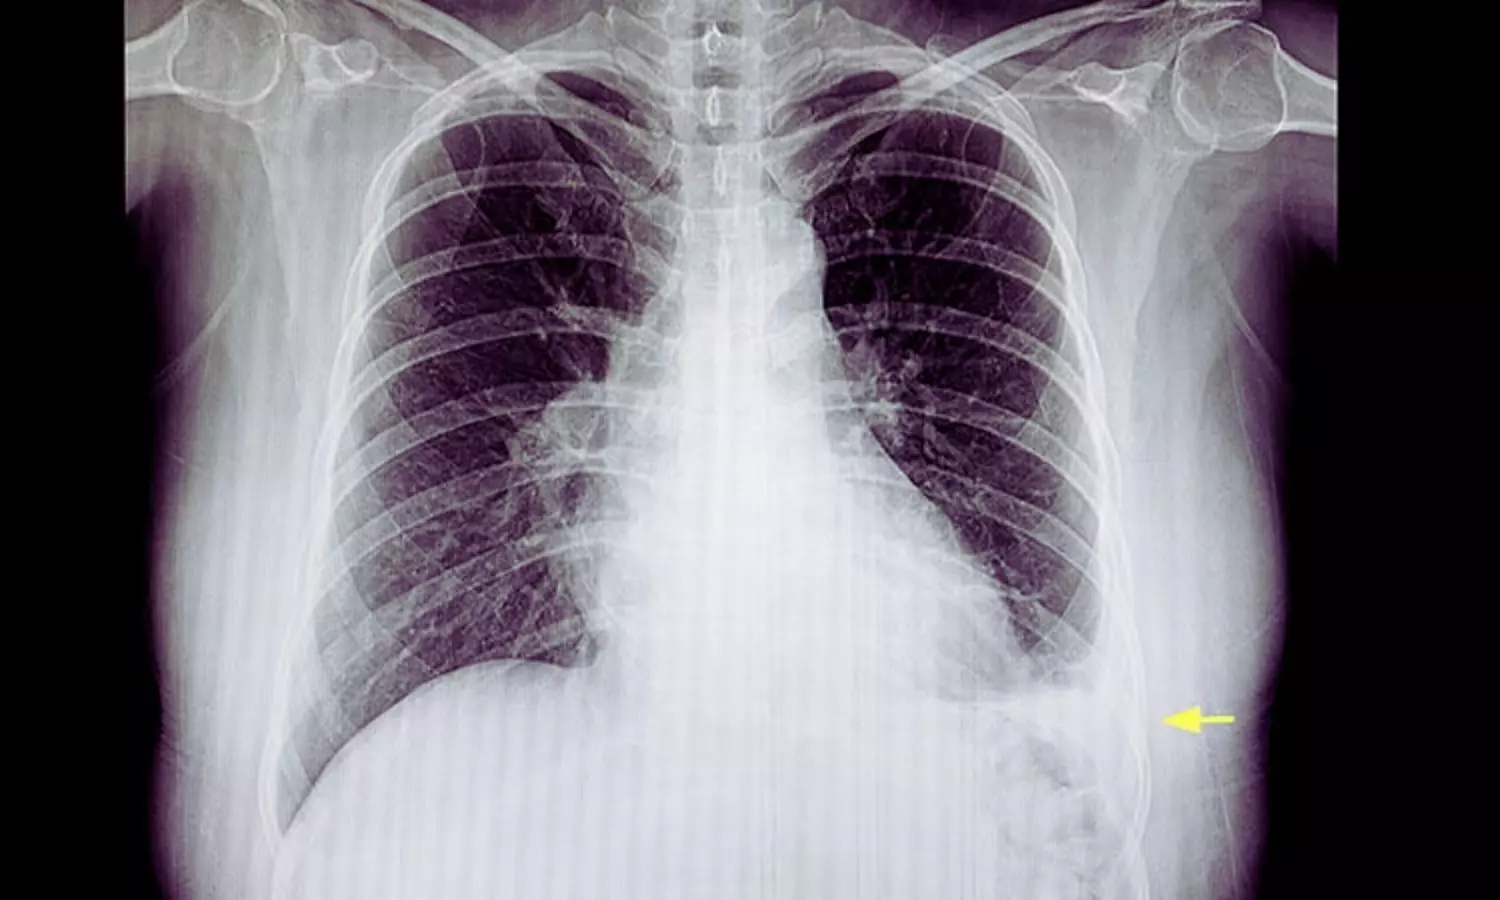

Intrapleural Enzyme Therapy Outperforms Saline Lavage in Pleural Infection: SCOPE Trial

Spain: A study published in the European Respiratory Journal reports that saline lavage alone may prolong pleural drainage in patients with pleural Infection compared with intrapleural enzyme therapy (IET). The findings also indicate that adding saline lavage to IET does not provide a meaningful clinical advantage over enzyme therapy alone.

- Saline lavage alone was associated with a longer pleural drainage duration compared with enzyme-based treatment.

- The median drainage duration was 4 days in the saline-only group versus 3 days in both the intrapleural enzyme therapy (IET) alone and saline-plus-IET groups.

- Early radiographic improvement was similar across all treatment groups.

- By day 2, all groups showed a median reduction of about 30% in pleural effusion size.

- By day 5, patients receiving enzyme therapy demonstrated greater pleural fluid resolution, with a median residual effusion of zero.